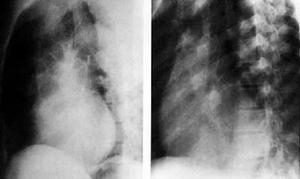

超聲心動圖檢查:M型超聲心動圖顯示左心房、右心室增大,二尖瓣前瓣葉曲線舒張期E峰後緩慢下降,BE波下降速度減慢,呈現城牆垛樣圖像。由於瓣膜交界融合,前瓣葉與後瓣葉呈同向運動。切面超聲心動圖可顯示瓣膜增厚,活動度受限制,形態不規則,瓣口狹小,有時尚可顯示瓣下腱索增粗粘連。超聲心動圖尚可檢查左心耳、左心房內有無血栓,套用食管探頭檢查左心耳、左心房內血栓,診斷更為可靠。